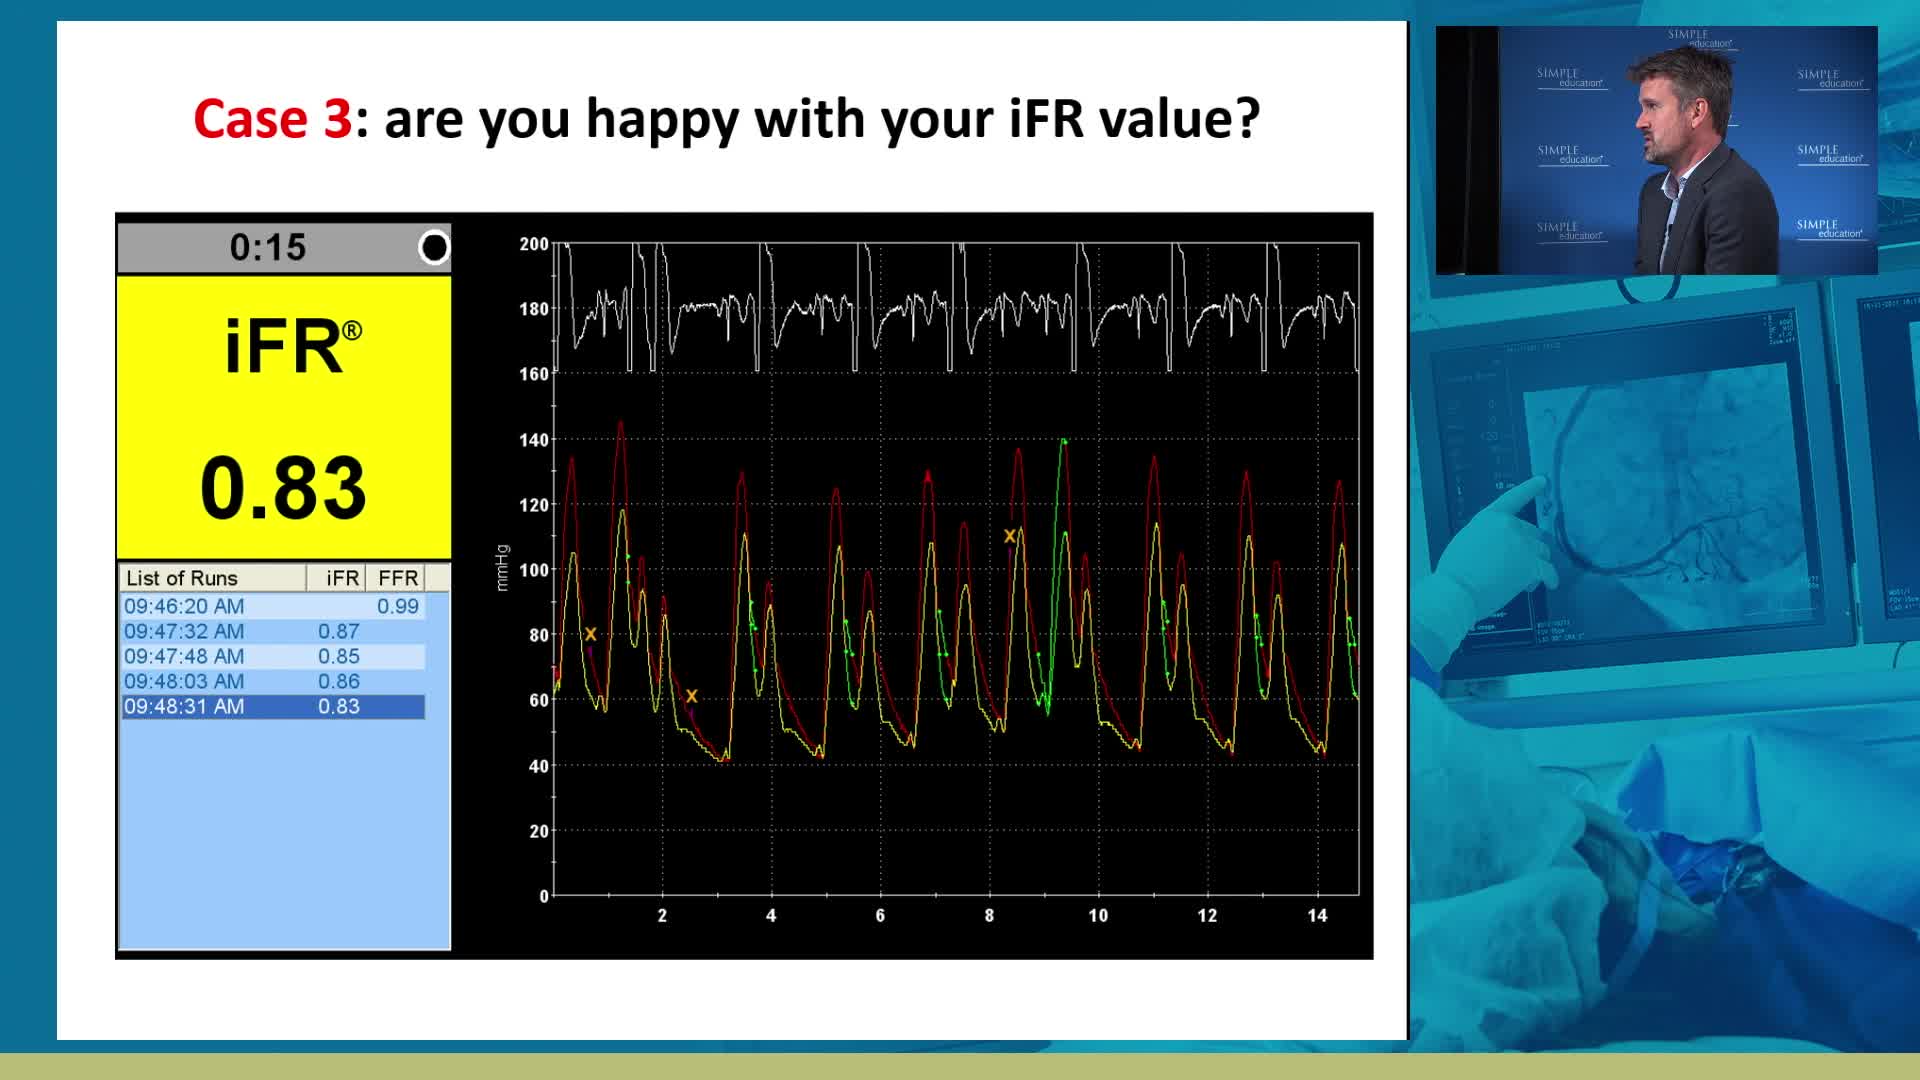

Breakout session: Common pitfalls of FFR and iFR assessment - Dr Ricardo Petraco

How to perform iFR and FFR, and best-practice measurement tips and tricks - Dr Ricardo Petraco